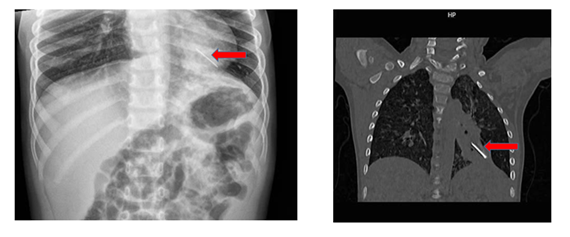

Hình ảnh chụp Xquang và đoạn kẽm nhung sau khi được bác sĩ phẫu thuật lấy ra ngoài

Bệnh nhi là bé T.T.N (3 tuổi, ngụ Đồng Tháp). Bệnh sử, trước 4 giờ nhập viện, bệnh nhi ho ra máu đỏ tươi 2 lần, gia đình không rõ nguyên nhân do nuốt hay hít dị vật. Ngay sau đó, bé được bệnh viện địa phương sơ cứu và tiếp tục chuyển tiếp đến Bệnh viện Nhi đồng Thành phố cấp cứu trong tình trạng khó thở, lừ đừ, môi tái.

Tại bệnh viện, chỉ số SpO2 còn 90%, nhịp thở nhanh, co kéo cơ hô hấp, phế âm bên trái giảm nhẹ. Kết quả chụp X-quang và CT scan ngực ghi nhận có dị vật cản quang tại thùy dưới phổi trái.

Các bác sĩ chẩn đoán trẻ bị dị vật phế quản trái và nhanh chóng tiến hành hỗ trợ hô hấp, dùng kháng sinh, đồng thời hội chẩn liên chuyên khoa. Nội soi đường thở ban đầu ghi nhận có tổn thương niêm mạc và máu trong đường thở. Trong quá trình can thiệp, tình trạng oxy máu của trẻ giảm, buộc ê-kíp phải tạm ngưng để hồi sức tích cực và truyền máu.

Sau đó, bệnh nhi được chỉ định phẫu thuật mở ngực khẩn cấp. Ê-kíp ngoại lồng ngực đã tiến hành mở phế quản gốc trái và lấy ra dị vật là một đoạn kẽm nhung dài khoảng 2 cm, dính máu cũ. Sau khi lấy dị vật, đường thở được làm sạch và khâu phục hồi.